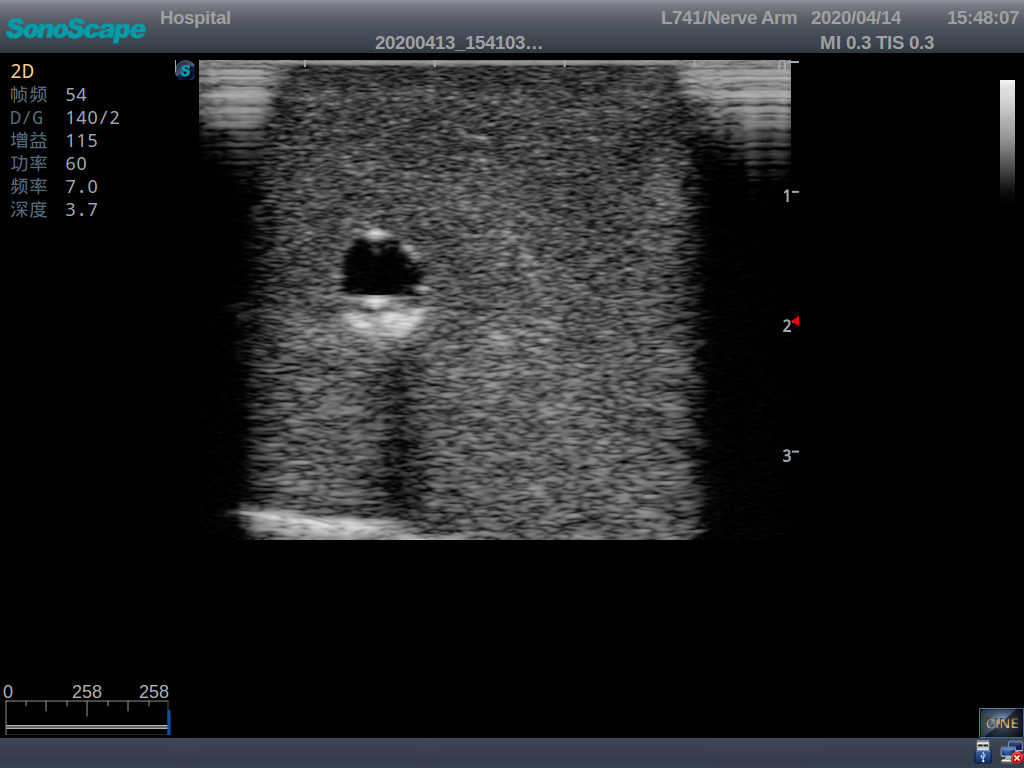

Model TYE1510.1

Product size(mm) 700×500×160

It is a model covering up from lobulus auriculae plane to the umbilical plane, and it has anatomical structures like clavicle, rib, sternocleidomastoid, jugular vein and basilic vein.

1)   Made of high molecular polymer ultrasound material, close to the real skin

2)   It can be used by real ultrasound machines

3)   Clear and real images of the tissues and organs (basilic vein and superior vena cava)

4)   When conducting vascular puncture, the piercing can be truly felt, and venous blood outflow can be seen

5)   Observe the guide wire marches

6)   Detect whether the catheter is properly placed